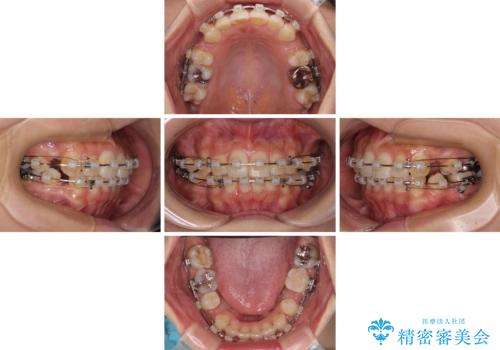

【モニター】閉じにくい前歯とクロスバイト ワイヤー装置での抜歯矯正

- 前歯のクロスバイトと口元の膨らんだ横顔の印象を気にして来院された患者様です。

ご本人の気にされている口元は、分析数値からするとそれほど突出しているものではありませんでした。

しかしながら。そのまま叢生を解消すると横顔が突出した印象になる可能性が高かったため、上下左右の小臼歯4本を抜歯して、ワイヤー装置にて矯正治療を行うこととしました。

上下左右の第一小臼歯4本を抜歯して治療を行うことがセオリーでしたが、左下は第二小臼歯が銀歯であったため、イレギュラーではありますが、そちらを抜歯しました。

その影響で治療期間は長くなりましたが、処置していない歯を保存することができました。